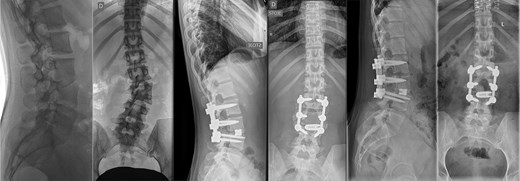

Last preoperative X-ray, lateral (A) and anteroposterior view (B). After 10 weeks of follow-up; lateral (C) and anteroposterior view (D). After 1 year of follow-up; lateral (E) and anteroposterior view (F).

Postoperatively, the patient experienced left psoas and quadriceps femoris muscle paresis, with the latter gradually improved to near-normal before discharge. No other complications were observed. At the 10-week follow-up, the left quadriceps had regained full strength, but partial paresis (3 out of 5) of the psoas muscle persisted, resulting in gait disturbance. At the final follow-up, one year after surgery, imaging showed L2-L4 fusion with no signs of instability or residual deformity (Fig. 4). The patient’s back pain resolved. A normal muscle function was observed.

CT-based 3D reconstruction revealed a semi-segmented hemivertebra at L3, resulting in a 32° Cobb angle of congenital scoliosis (Fig. 4). We decided to perform hemivertebra resection, L3 laminectomy, L2-L4 fixation with L3–4 cage fusion, and scoliosis correction. CT-based resection was 3D planned using EBS software (Fig. 6). Fixation from L2 to L4 was achieved using pedicle screws under fluoroscopic guidance, followed by L3 laminectomy. After accessing the L3–L4 disc space, a 3D real-time EMN-guided total resection of the L3 hemivertebra was performed (Fig. 6), and a cage with autogenous bone graft was inserted at the L3–L4 level. The left-sided L3 nerve was found to have an accessory branch, which was successfully preserved. Scoliosis was corrected using standard deformity correction maneuvers.